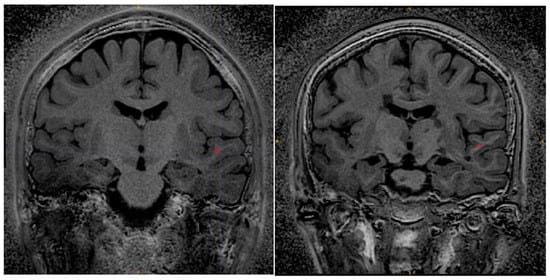

Figure 4 shows an example sagittal slice from the MS patient through the brain-stem. The blue circle outlines a brainstem lesion which is visible on the SilentMT image and the 1.5T FLAIR image, but difficult to see on the 7T FLAIR. Just above the blue circle, another brain-stem lesion can be seen. The 1.5T and 7T FLAIR images show this lesion as brighter than other local features whereas on the SilentMT image, the lesion appears as bright as the neighbouring CSF. A qualitative visual assessment of the SilentMT image is that there is strong contrast between CSF, grey matter, and white matter, reminiscent of what is seen in T2-weighted images. Image contrast appeared relatively uniform across the cerebrum and cerebellum, and so less affected by the transmit B1 inhomogeneity typically observed in the head at 7T.

Figure 4. Brain-stem lesions. Brain-stem lesion (blue circle) observed on 1.5T FLAIR (left). FLAIR 7T contrast is strongly affected by transmit B1 inhomogeneity—MS lesion is very faint (centre). SilentMT contrast is robust against transmit B1 inhomogeneity—lesion observed (right). Red circle shows region affected by trajectory errors in SilentMT.

The Silent images showed some “trajectory error” geometric distortion in areas of strong B0 inhomogeneity such as can be observed at the base of the brain in Figure 4 (red circle).